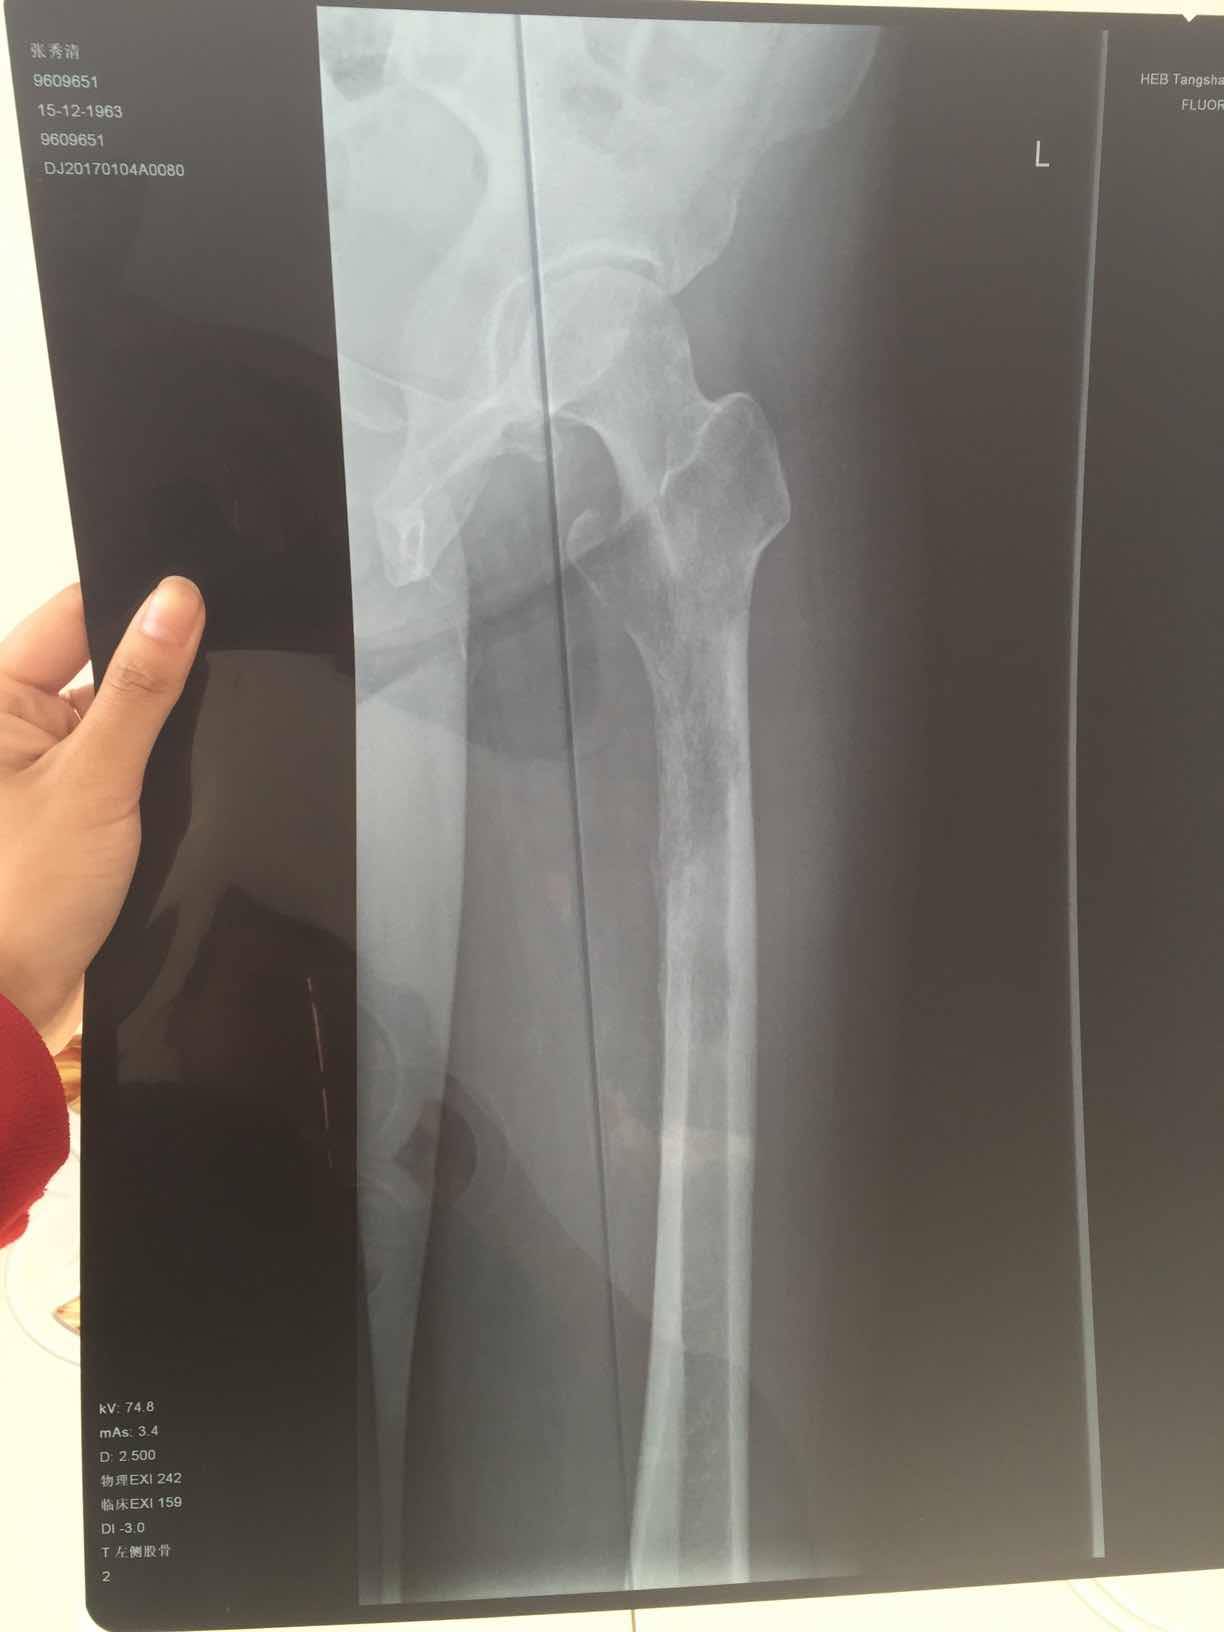

这是第一次确诊是拍的腿部ct,因为是腿疼才去检查,直接去的骨科医院,没想到确是转移,主要是左大腿疼痛,在家以为是腰间盘卧床躺了3月,期间就第三个月疼痛无比,刚开始两月还好,也能行走,就是腿疼,尽量不走,等再去医院检查的当天还把左大腿根掰了下,可能造成了骨裂,图片为最后一张图画圈的那里,打了两次骨转针。吃了一个月易瑞沙,腿已经不疼了,但是由于骨裂那块,还是卧床不让行走,医生也说让静养,怕骨折。我想问问大家有没有这方面的,我家这个情况该怎么办。还有机会在站起来行走吗,目前左腿肌肉萎缩的还比较厉害,拜托大家。